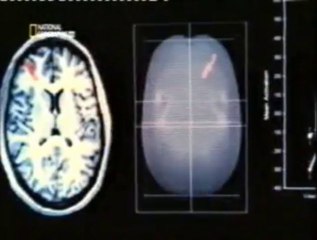

El evento “Conocé tu cerebro y toma decisiones” reunió a destacados expertos en neurociencia cognitiva y coaching ontológico, incluyendo al Dr. Jorge Hirsch, junto a la presencia de Natalia Ferreira de SCOP y Oscar Maidana de MCOP. Durante esta jornada, se exploraron las conexiones entre el funcionamiento del cerebro y la toma de decisiones, ofreciendo una perspectiva integral para el desarrollo personal y profesional.